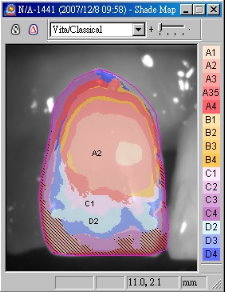

經過四週後,由於傷口癒合良好,準備製作假牙,由於是前牙區,因此顏色相當重要,因此使用數位比色(圖七)及數位攝影(圖八),取得牙齒之精確顏色分佈。

圖七 |